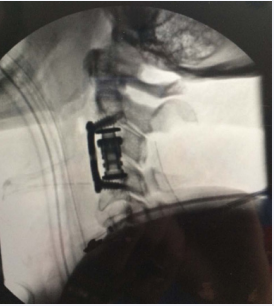

and the patient was taken to the operating room for emergent decompression. A posterior decompression from C2-C4 was initially performed, followed by a corpectomy of C3, placement of an interbody cage, and anterior spinal fusion from C2-C4 (Figure 3).

Figure 3: Demonstrates intra-operative fluoroscopic lateral cervical spine radiograph of the posterior decompression of C2-4 and C3 corpectomy with cage placement and anterior spinal fusion from C2-4.